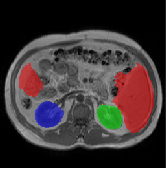

Datasets and Evaluation Metrics. We evaluate our method on three public datasets: (1) ACDC [19]: Cine-MRI images from 100 patients, with manual annotations for the Right Ventricle (RV), Left Ventricle (LV), and Myocardium (MYO). The dataset is divided into 70 training, 15 validation, and 15 testing cases. (2) MSCMRseg [29]: Late Gadolinium Enhancement (LGE) MRI scans from 45 cardiomyopathy patients, annotated for the RV, LV, and MYO, are divided into 25 training, 5 validation, and 20 testing cases. (3) CHAOS [10]: T1-weighted abdominal MR images from 20 subjects with liver, kidney, and spleen, split into 70% training, 15% validation, and 15% testing cases. For scribble annotations, the ACDC dataset uses manually created scribbles [19], while MSCMRSeg and CHAOS datasets use ITK-Snap to annotate 1-pixel-wide scribbles [5]. All results are based on 5-fold cross-validation, evaluated using the Dice coefficient and 95% Hausdorff Distance (HD95).